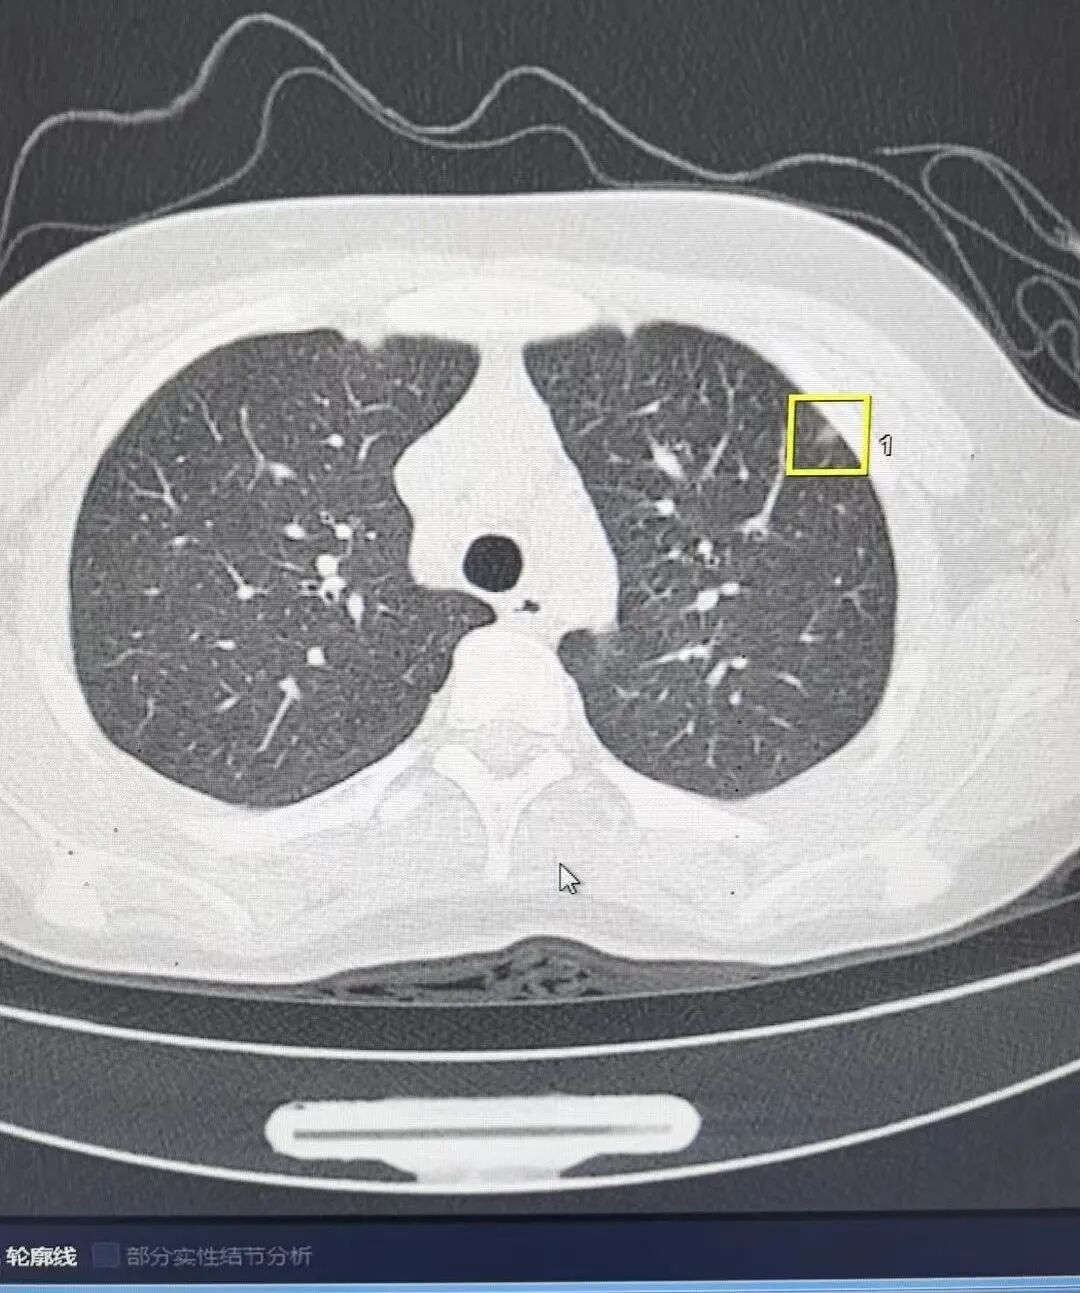

此外,我院放射科还开展了胸部低剂量肺结节筛查,肺结节CT低剂量扫描+三维重建技术将大大提高对肺结节病变的诊断效率与精准程度。

联影ct怎么样杞县中心医院影像诊断“利器”——联影高端螺旋CT_https://www.jmylbn.com_新闻资讯_第3张

肺结节电脑自动分析